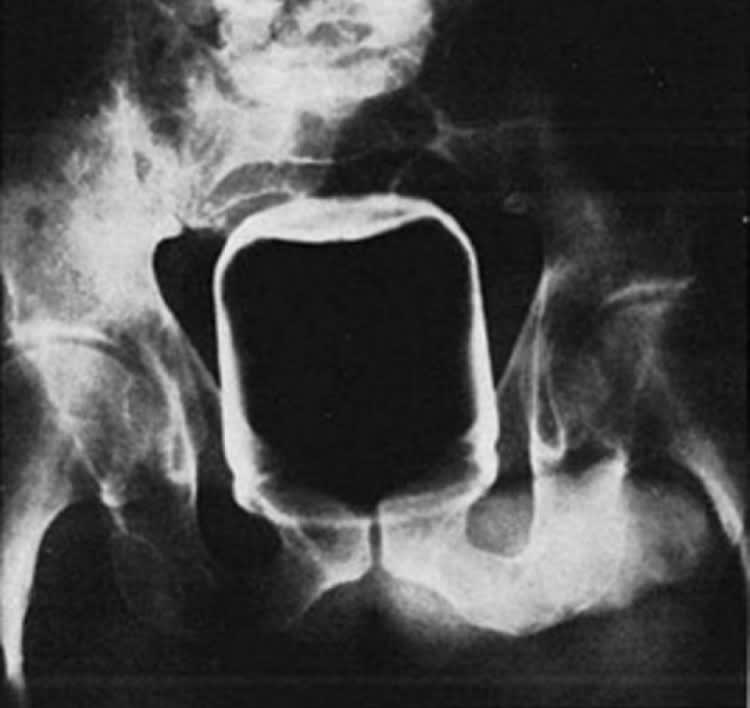

Petit jeu : le premier qui a trouvé l'ensemble des éléments coincés , a gagné 😊

la K7 c'est trop 80's la barbie aussi, non?

Le buzz l'eclair, les ailes étaient ouvertes ou repliées?

T'as triché . 😊Buzz l'éclair il était impossible à retrouver.